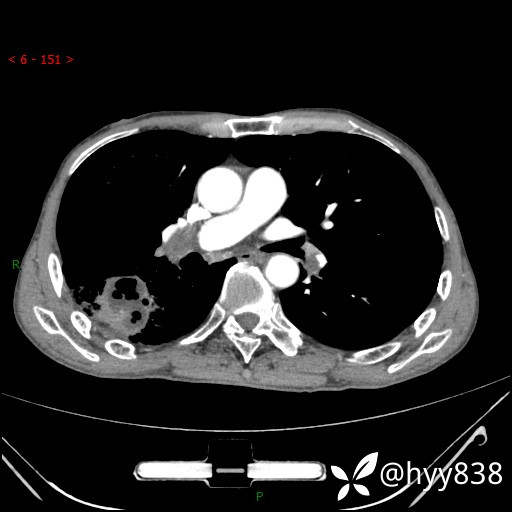

胸部CT平扫